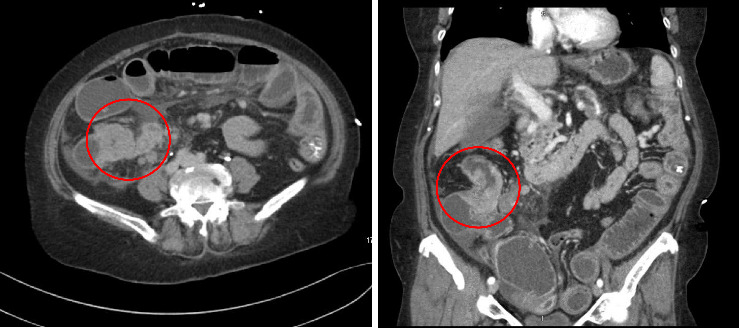

结直肠癌转移到十二指肠是非常罕见的,并提出了重大的诊断和治疗挑战。我们描述了一位68岁的女性右结肠腺癌患者,尽管接受了FOLFOX化疗,但仍发生了十二指肠转移。向FOLFIRI的过渡取得了有限的成功,强调了创新方法的必要性。遗传分析显示KRAS G12D突变,针对该突变的靶向治疗尚未获批。免疫组织化学证实十二指肠肿块起源于胃肠道。文献表明,手术切除可以提供治疗潜力,在某些情况下,虽然它是不可行的。新兴的kras靶向药物,如MRTX1133,代表了解决这种突变的有希望的选择。该病例强调了管理罕见转移模式的挑战,个性化治疗的潜力,以及进一步研究晚期结直肠癌创新治疗的必要性。它强调了制定有针对性的策略来改善这种复杂转移性疾病患者预后的重要性。

Metastasis to the duodenum from colorectal cancer is exceptionally rare and presents significant diagnostic and therapeutic challenges. We describe a 68-year-old female with right colon adenocarcinoma, who developed a duodenal metastasis despite treatment with FOLFOX chemotherapy. Transition to FOLFIRI yielded limited success, emphasizing the need for innovative approaches. Genetic analysis revealed a KRAS G12D mutation, for which targeted therapies are not yet approved. Immunohistochemistry confirmed the gastrointestinal origin of the duodenal mass. Literature indicates that surgical resection can offer curative potential in select cases, although it was not viable here. Emerging KRAS-targeted agents, such as MRTX1133, represent promising options for addressing this mutation. This case underscores the challenges of managing rare metastatic patterns, the potential of personalized therapies, and the necessity for further research into innovative treatments for advanced colorectal cancer. It highlights the importance of developing targeted strategies to improve outcomes for patients with such complex metastatic diseases.